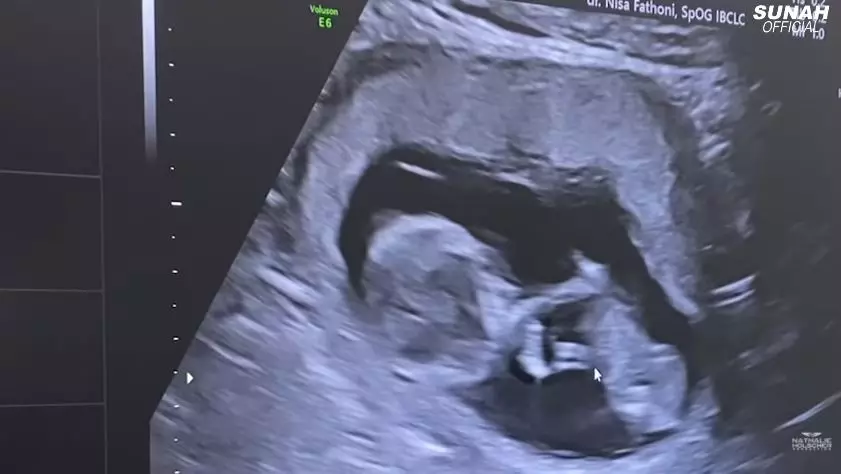

3. Sesampainya di rumah sakit, Nathalie pun langsung melakukan USG untuk melihat perkembangan janinnya.

1. Kini usia kandungan Nathalie Holscher telah menginjak 13 minggu. Ia pun cukup rutin memeriksakan kondisi kehamilannya.

Kini, usia kehamilan Nathalie telah menginjak 13 minggu. Bersamaan dengan itu, ia tampak rutin memeriksakan kondisi janin yang dikandungnya. Setelah melalui pemeriksaan dokter, Nathalie pun mengetahui jenis kelamin calon buah hatinya.